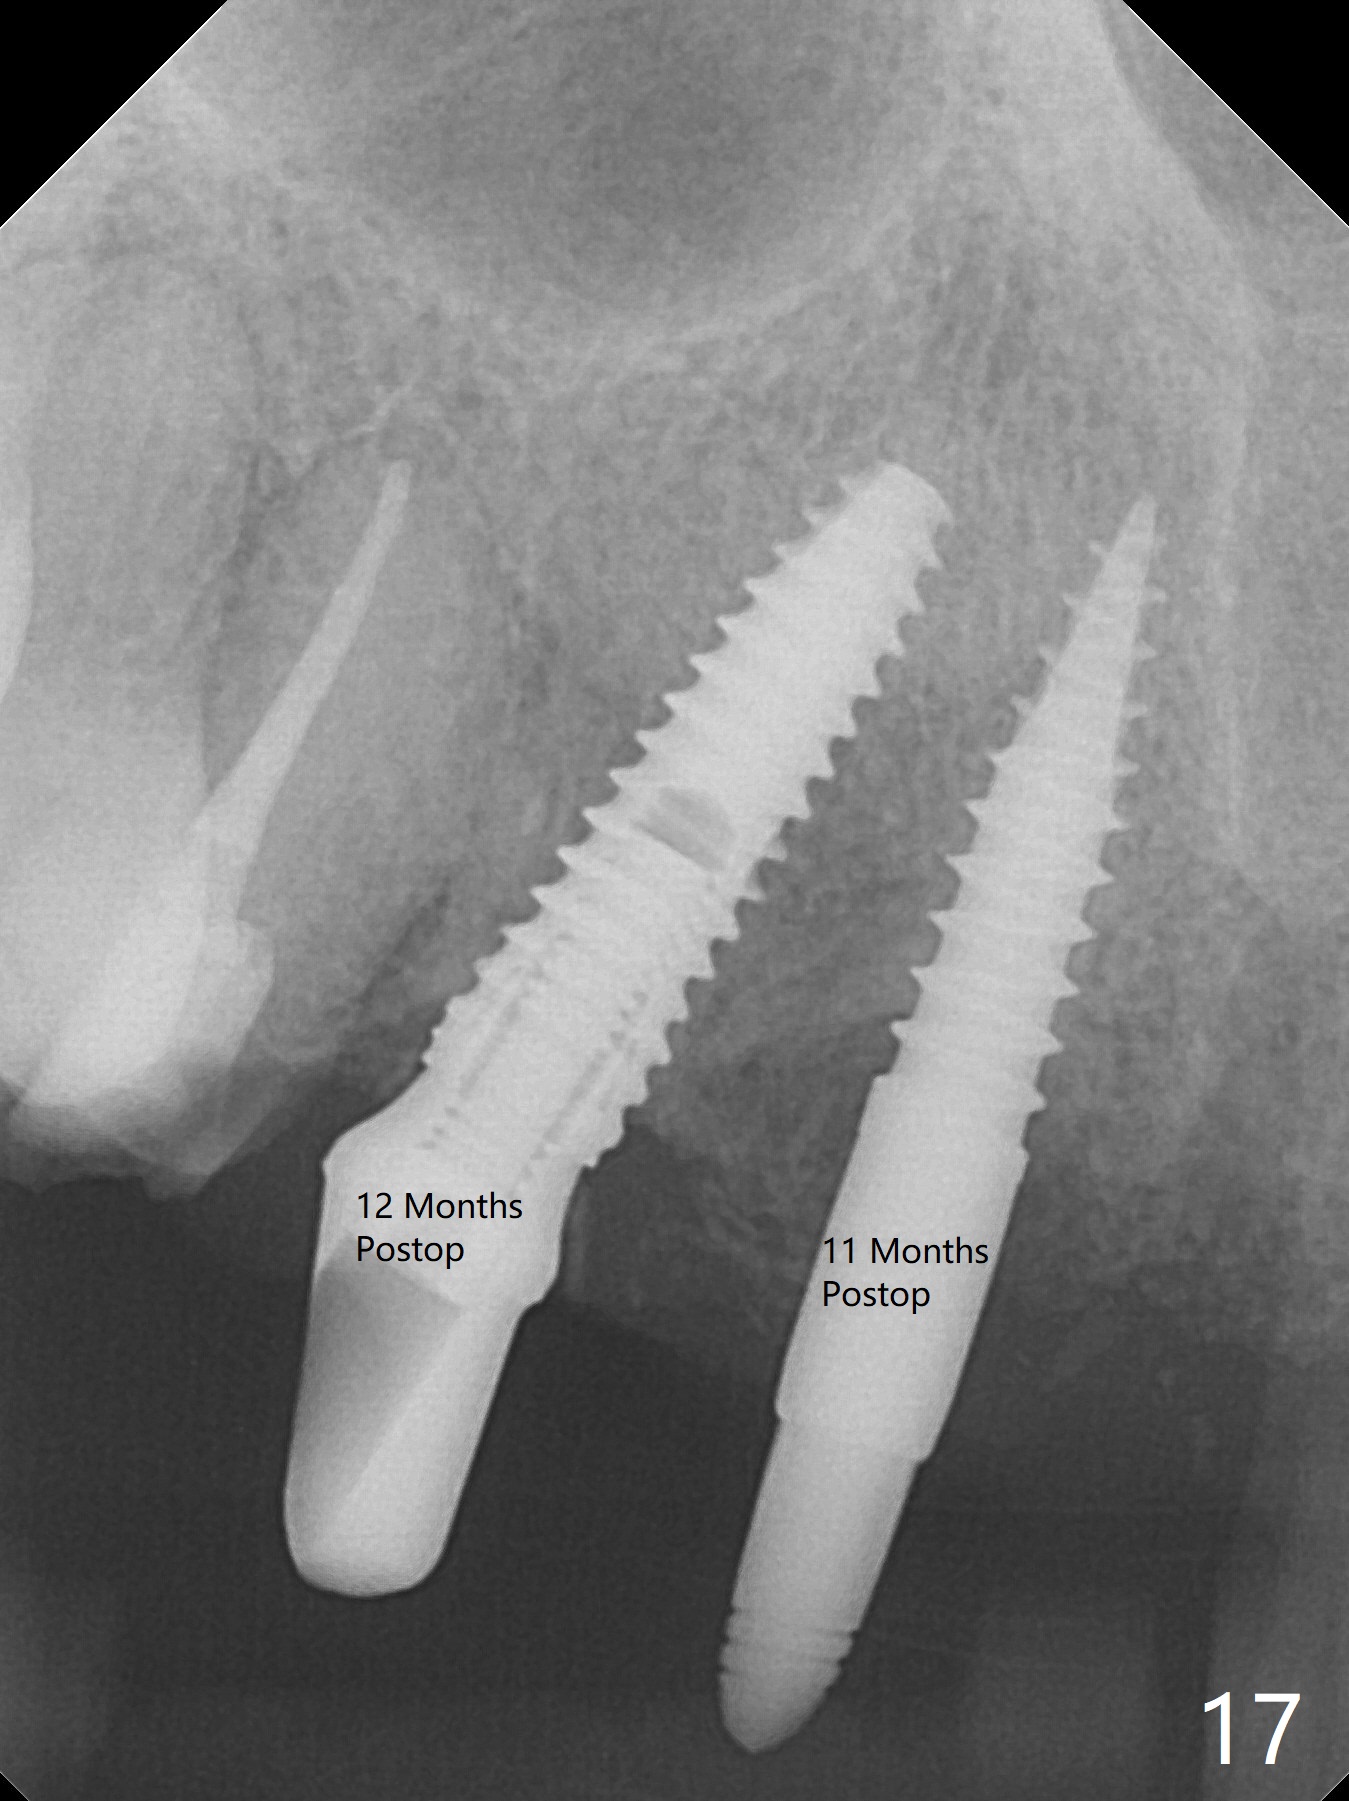

To have enough clearance for the splinted provisional at #6-12 (Fig.1 *), composite has been placed in the posterior teeth (bilateral, *, Fig.2). When the composite is removed, there is no clearance between the implants/abutments of #7 or 10 (Fig.3). Incision is made with removal of the 1-piece implant at #7; there is enough bone to move the osteotomy buccal (Fig.4 arrowhead). When the same implant is placed buccal (Fig.5), there is sufficient clearance for restoration (Fig.6 *), while there is still enough buccal bone left (Fig.7). When the patient returns 5.5 (for #7 and 10)/6.5 (#6,11,12) months postop, his chief complaint is tenderness lingual to #11. In fact, the abutment screw is loose at #11, while the implant at #10 has mobility (Fig.8), which is related to loss of the posterior stops (*) due to wear. There is slight bone loss mesial to #10 implant 5.5 months postop (Fig.10, as compared Fig.9). CBCT taken 5.5/6.5 months postop shows no bone loss (Fig.11-15). The 3x14 mm 1-piece implant at #10 is mobile 9 months postop and is removed and replaced by a 3.5x13 mm 2-piece one with slightly buccal osteotomy (Fig.16). PAs are taken prior to impression (Fig.17,18). The abutment at #12 is loose (<). More composite needs to be added to the occlusal surface of the upper posterior teeth. Finally the patient agrees to have crowns for the upper posterior teeth.